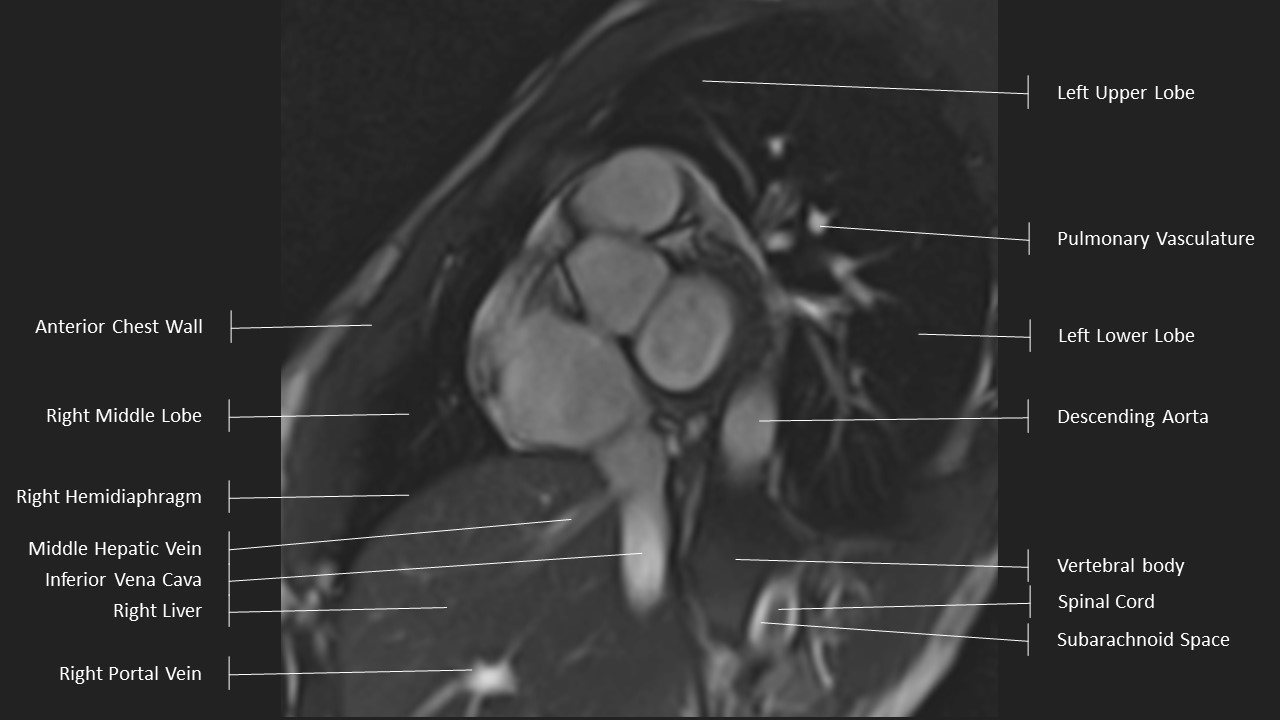

Short Axis Series

Axial Series